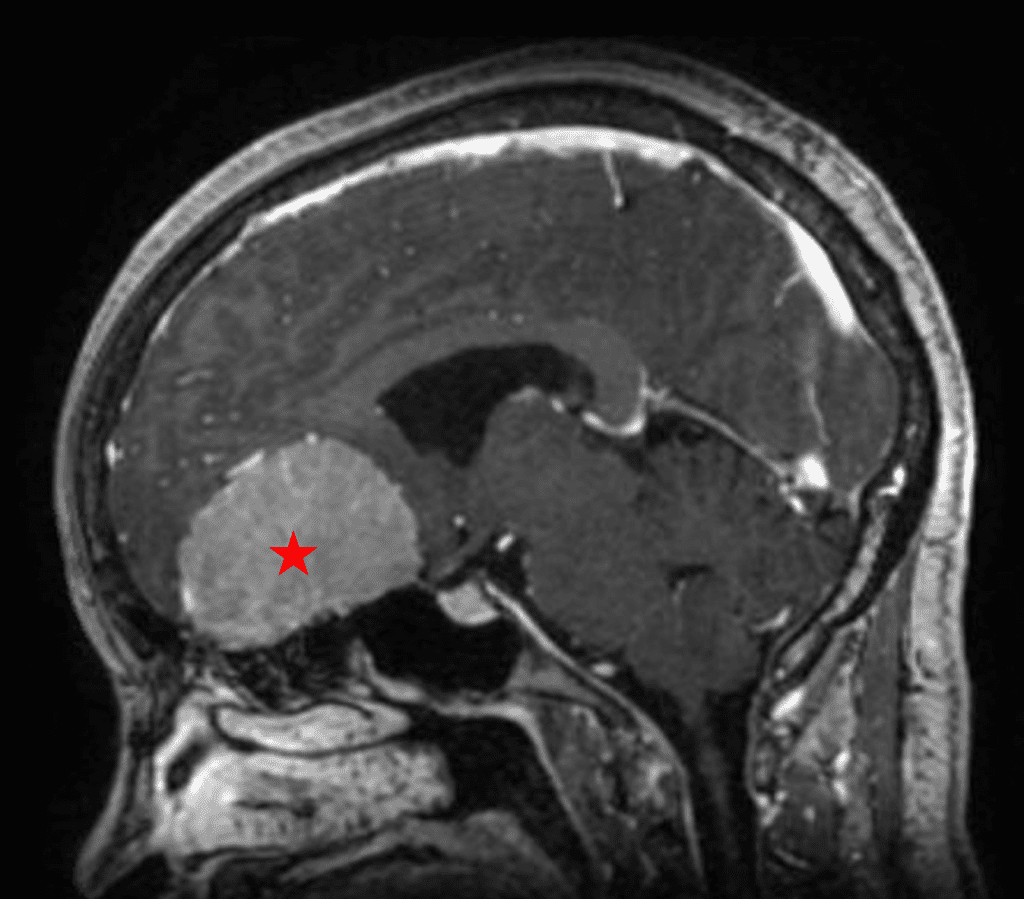

This is a 49-year-old otherwise healthy female who presented with bifrontal and retro-orbital headaches, behavioral changes, and forgetfulness. Symptoms have been progressively worsening over the past month. Her neurologic exam revealed a pronator drift, otherwise was unremarkable. MRI brain demonstrated a large extra-axial homogeneously enhancing mass of the anterior cranial fossa, resulting in significant mass effect and vasogenic edema (Figure 1a and 2a). Imaging was most consistent with a planum sphenoidale meningioma. She was referred to Dr. Xavier Gaudin for neurosurgical evaluation.

Figure 1a – Preoperative MRI demonstrating an extra-axial enhancing mass of the anterior cranial fossa.

She was started on high-dose steroid and antiseizure prophylactic medicine. Surgical intervention was offered for mass effect, symptomatic relief, neurologic preservation, and histopathologic diagnosis. Dr. Gaudin performed a bifrontal craniotomy with complete resection of neoplasm through an interhemispheric and subfrontal approach. Postoperative imaging demonstrated a gross total resection without residual tumor and resolution of mass effect (Figure 1b and 2b). Intraoperative pathology was consistent with meningioma, WHO grade 1. She recovered very well, and was discharged home on postoperative day 3. On her follow-up outpatient visit, her preoperative symptoms had fully resolved, and her olfactory sense was maintained.

Figure 2a – Preoperative MRI demonstrating an extra-axial lesion with surrounding vasogenic edema and mass effect on the frontal lobes.